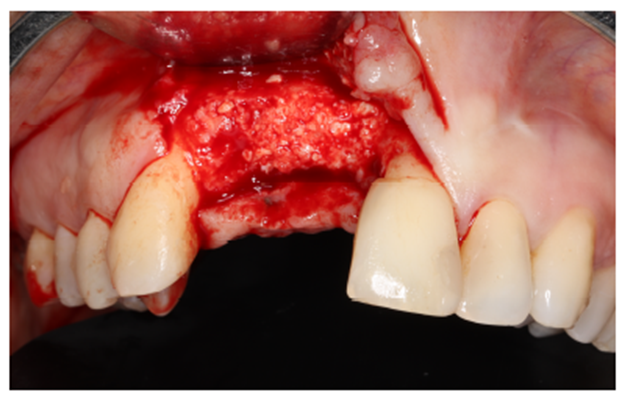

Nos casos de extensa reconstrução óssea, o retalho cirúrgico deve ser realizado à distância para visualização total da área cirúrgica, acomodação do seu futuro material de enxerto, ganho e fechamento total do tecido mole (Figura 4). Outro ponto importante para o sucesso da integração do material de enxerto é a descorticalização do processo alveolar, a fim de levarmos sangue medular com maior quantidade de células osteoprogenitoras. No caso, foi realizado com uma broca tipo lança.